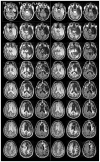

It has been proposed that self-awareness (SA), a multifaceted phenomenon central to human consciousness, depends critically on specific brain regions, namely the insular cortex, the anterior cingulate cortex (ACC), and the medial prefrontal cortex (mPFC). Such a proposal predicts that damage to these regions should disrupt or even abolish SA. We tested this prediction in a rare neurological patient with extensive bilateral brain damage encompassing the insula, ACC, mPFC, and the medial temporal lobes. In spite of severe amnesia, which partially affected his "autobiographical self", the patient's SA remained fundamentally intact. His Core SA, including basic self-recognition and sense of self-agency, was preserved. His Extended SA and Introspective SA were also largely intact, as he has a stable self-concept and intact higher-order metacognitive abilities. The results suggest that the insular cortex, ACC and mPFC are not required for most aspects of SA. Our findings are compatible with the hypothesis that SA is likely to emerge from more distributed interactions among brain networks including those in the brainstem, thalamus, and posteromedial cortices.